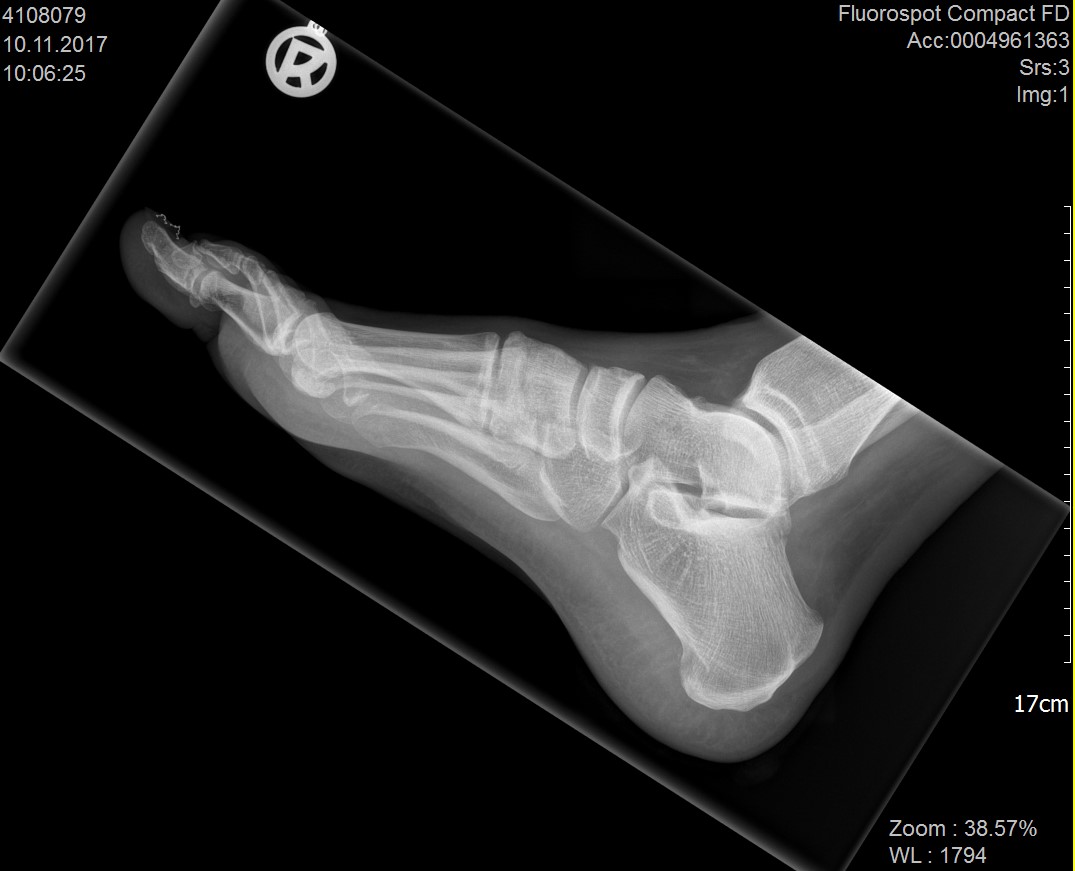

Abbildung 1: Plantarer und dorsaler Sporn im Röntgenbild und im MRT

Abb. 1a und Abb. 1b: großer dorsaler Fersensporn und ein minimaler plantarer Sporn, Patient, 50 Jahre.

Abb. 1c: Bild eines isolierten großen plantaren Fersensporns. Patientin, 32 Jahre.

Zum Lesen der Bildbeschreibung und zur Vollansicht bitte die Bilder anklicken. Bilder: Manfred Thomas.

Mit Hilfe von  Röntgenaufnahmen können knöcherne Abnormalitäten und Achsfehlstellungen ausgeschlossen werden. Folgen von Unfällen, wie zum Beispiel fehlverheilte Fersenbeinfrakturen oder überstehende Schrauben oder Platten nach osteosynthetischen Verfahren am Fersenbein können als Ursachen für plantare Beschwerden an der Ferse ausgeschlossen werden.

Konventionelles Röntgen (Fersenbein seitlich und tangential)

Arthrose der Fußwurzelgelenke, osteophytäre Ausziehung, plantarer oder dorsaler Fersensporn, Auffälligkeiten nach Unfällen oder Operationen (Fehlstellung, fehlpositioniertes Osteosynthesematerial, Fremdkörper), Veränderungen der Knochenstruktur (Ermüdungsfraktur, Osteoporose, Tumoren, etc.)

Dorsaler Fersensporn: Dorsale Fersenschmerzen können auch durch einen echten dorsalen Fersensporn entstehen (siehe Abb. 1). Dieser entsteht als knöcherne Ausziehung durch Verkalkung der Achillessehne an ihrem Ansatz.